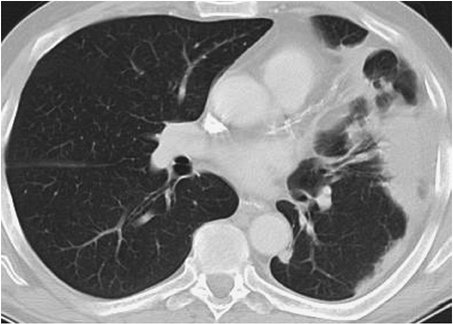

FIGURE 12-9. Pulmonary infarcts. CT of a 69-year-old man 10 weeks after a confirmed acute pulmonary embolic event shows residual subpleural scarring related to bilateral pulmonary infarcts (arrows).